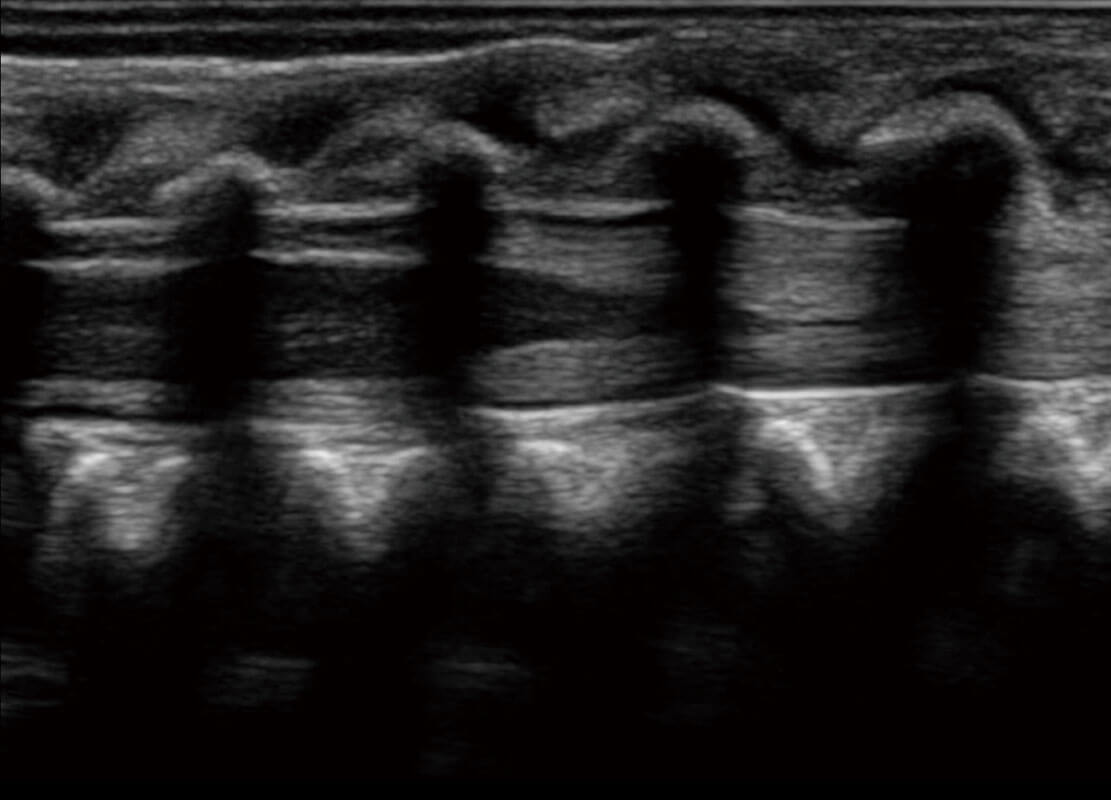

胎心筛查

P60搭载一系列胎儿心脏成像技术,实现精细的胎儿心脏评估。

• 四腔切面

• 四腔心血流